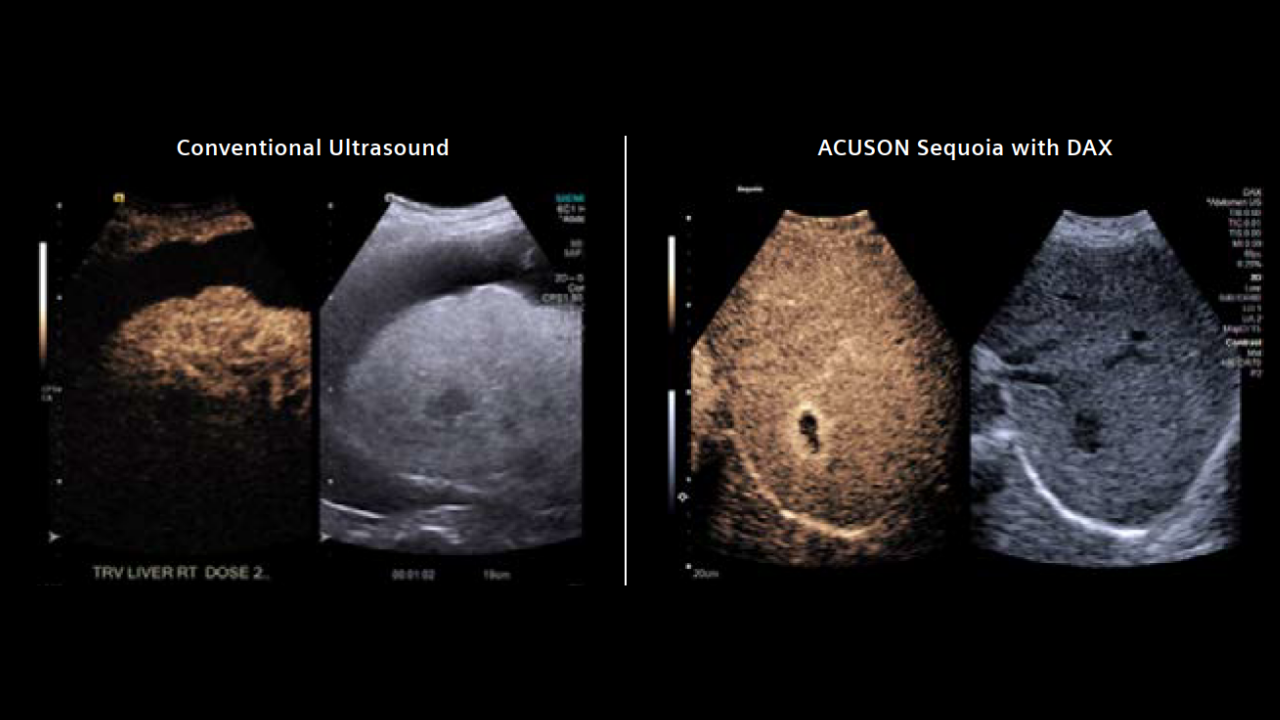

Every patient deserves a definitive ultrasound, even when the exam is difficult. The DAX Deep Abdominal transducer for ACUSON Sequoia brings clarity at depth and consistent visualization of deep anatomy while reducing the force needed to scan.

In high-BMI and technically challenging cases, it helps elevate B-mode and Doppler performance and works seamlessly with advanced applications such as shear wave elastography, Ultrasound-derived Fat Fraction, and contrast-enhanced ultrasound. The result is a gentler exam, clearer answers, and decisions made with confidence.

Radiology departments are often challenged by obesity and conventional technology that can limit diagnostic accuracy due to deep vessels, deep lesions, or severe disease.